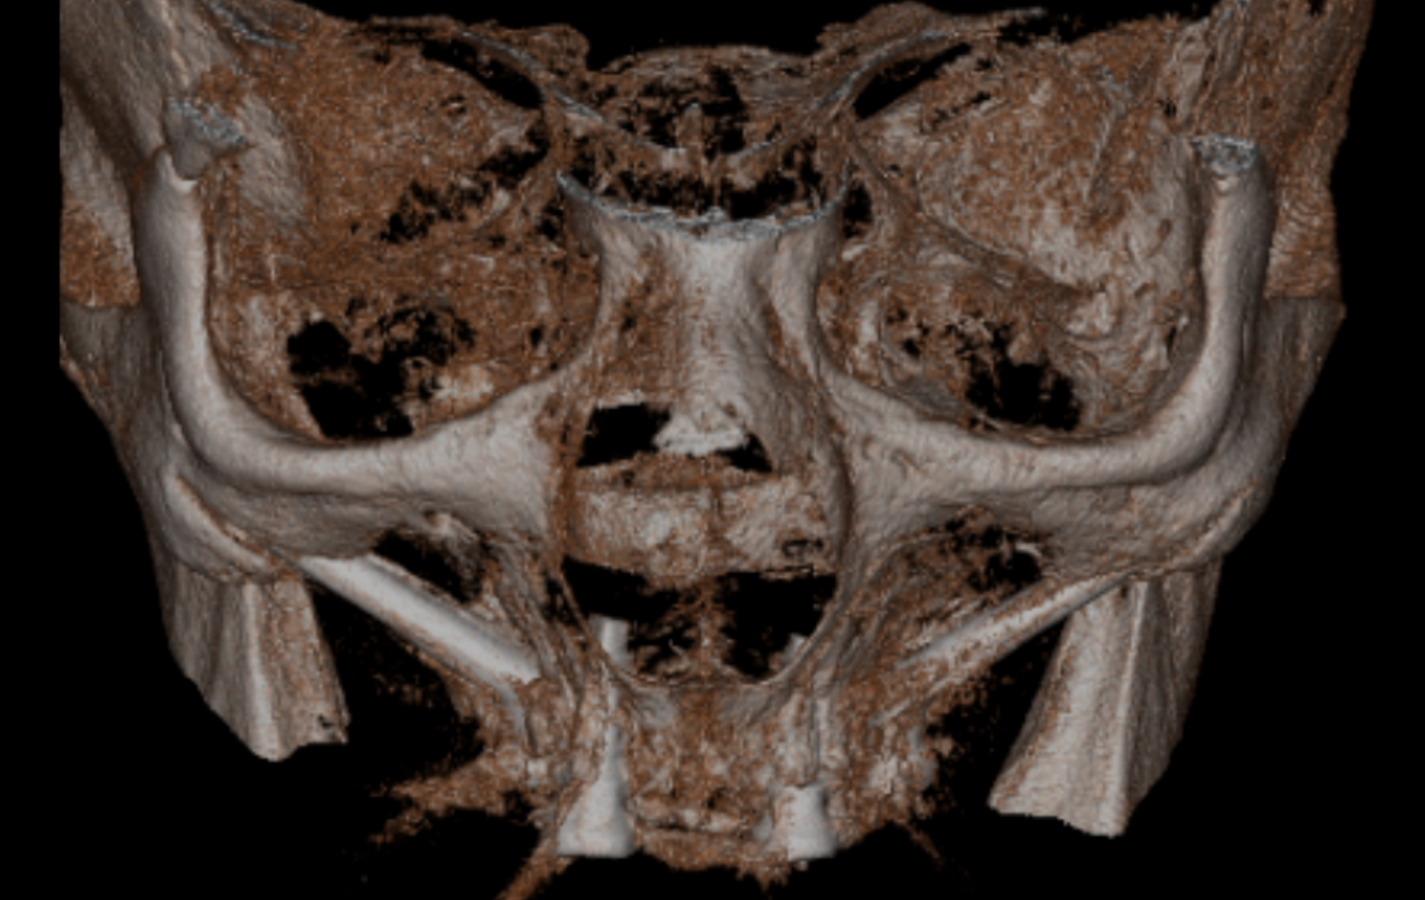

Een 80-jarige patiënte, bekend met gebruik van bloedverdunners, presenteerde zich met functionele en esthetische klachten door volledig uitneembare prothesen in boven- en onderkaak die zij al >40 jaar droeg. De prothesetanden waren sterk versleten en zowel retentie als stabiliteit was matig, wat leidde tot kauwproblemen en verminderd comfort. Klinisch en radiologisch werd een zeer ernstige resorptie vastgesteld in zowel de maxilla als de mandibula, passend bij Cawood & Howell-classificatie V–VI (figuur 9-11).

CBCT-scan preoperatief.

Postoperatieve CBCT-scan.